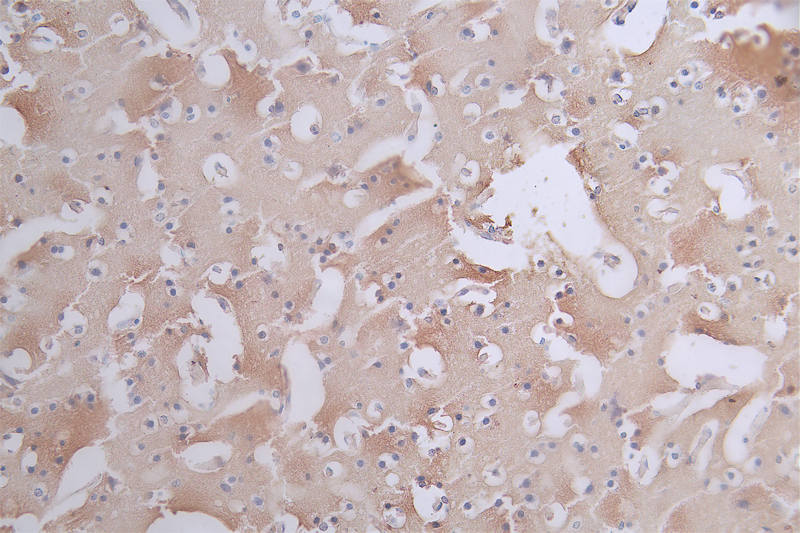

IHC image of CSB-RA901354A0HU diluted at 1:50 and staining in paraffin-embedded human brain tissue performed on a Leica BondTM system. After dewaxing and hydration, antigen retrieval was mediated by high pressure in a citrate buffer (pH 6.0). Section was blocked with 10% normal goat serum 30min at RT. Then primary antibody (1% BSA) was incubated at 4°C overnight. The primary is detected by a Goat anti-rabbit polymer IgG labeled by HRP and visualized using 0.11% DAB.

產(chǎn)品描述:Phospho-MAPT (S404) Recombinant Monoclonal Antibody(CSB-RA901354A0HU)是一種高特異性抗體,靶向微管相關(guān)蛋白tau(MAPT)在絲氨酸404位點的磷酸化修飾。MAPT蛋白主要參與神經(jīng)元微管的組裝與穩(wěn)定性調(diào)節(jié),其異常磷酸化與神經(jīng)纖維纏結(jié)的形成密切相關(guān),尤其在阿爾茨海默病、進(jìn)行性核上性麻痹等神經(jīng)退行性疾病的病理進(jìn)程中起關(guān)鍵作用。該抗體經(jīng)嚴(yán)格驗證,適用于ELISA和免疫組化(IHC)實驗,其中IHC推薦使用稀釋比例為1:50至1:200,可在人腦組織樣本中精準(zhǔn)檢測S404位點的磷酸化狀態(tài),呈現(xiàn)高信噪比與清晰的定位信號。實驗數(shù)據(jù)顯示,該抗體對磷酸化表位具有高度選擇性,與非磷酸化或其他磷酸化位點的交叉反應(yīng)性極低??蒲蓄I(lǐng)域可將其應(yīng)用于神經(jīng)退行性疾病模型的病理機(jī)制研究、磷酸化tau蛋白的時空分布分析,或作為評估tau蛋白異常修飾的分子工具,為疾病相關(guān)信號通路探索及潛在治療靶點驗證提供可靠支持。

Application Recommended Dilution IHC 1:50-1:200 -